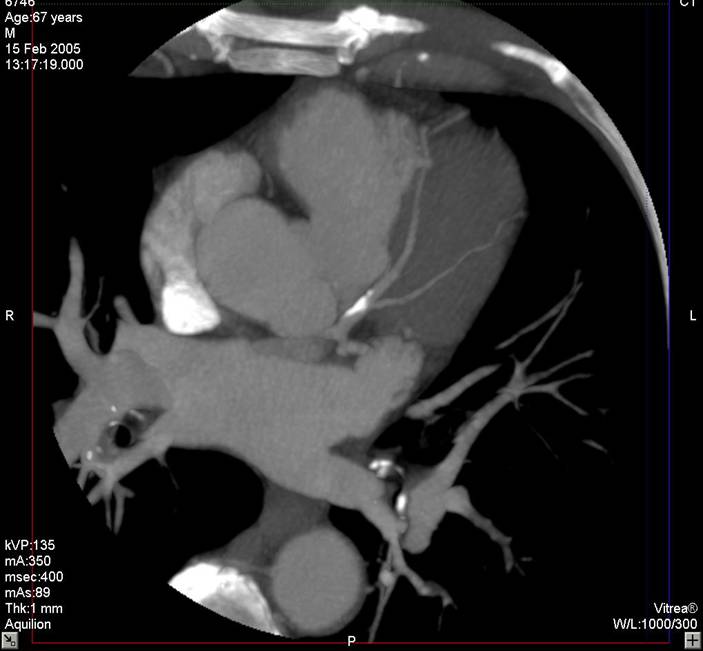

The non-invasive imaging modality of multi-detector computed tomography has dramatically evolved the last ten years and that is due to hardware and software developments. The newer generation of scanners allows increased spatial and temporal resolution that improves the clinical reliability giving further insights into the evaluation of coronary artery disease. Heart morphology imaging followed by studies of myocardial function and assessment of cardiac valves can be performed from the information derived from the data of the coronary artery examination. Also, the venous anatomy of the heart, coronary artery bypass grafts, stents, and cardiac tumors can be imaged and evaluated when necessary. For the beneficial use of this method, entrance criteria for different patient groups need to be set in order to allow improved outcome of multi-detector CT.